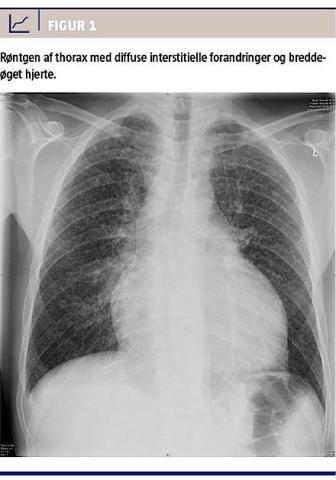

Ved indlæggelsen fandt man iltsaturation 94% uden ilttilførsel, respirationsfrekvens 30/min, normale forhold ved lungestetoskopi , en leukocytkoncentration på 4,6 mia./l (referenceinterval: 3,5-8,8 mia./l) og en koncentration af C-reaktivt protein på 65 mg/l (referenceinterval: 0,0-8,0 mg/l). På røntgen af thorax fandt man talrige interstitielle forandringer diffust i begge lunger og breddeøgning af hjertet (Figur 1); begge fund var tilkommet efter en kontrol to måneder tidligere.